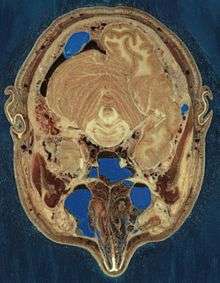

Cryosection through the head of a human male.

The Visible Human Project is an effort to create a detailed data set of cross-sectional photographs of the human body, in order to facilitate anatomy visualization applications. A male and a female cadaver were cut into thin slices which were then photographed and digitized. The project is run by the U.S. National Library of Medicine (NLM) under the direction of Michael J. Ackerman. Planning began in 1986;[1] the data set of the male was completed in November 1994 and the one of the female in November 1995. The project can be viewed today at the National Museum of Health and Medicine near Washington, DC. There are currently efforts to repeat this project with higher resolution images but only with parts of the body instead of a cadaver.

The male cadaver was encased and frozen in a gelatin and water mixture in order to stabilize the specimen for cutting. The specimen was then “cut” in the axial plane at 1 millimeter intervals. Each of the resulting 1,871 “slices” was photographed in both analog and digital, yielding 15 gigabytes of data. In 2000, the photos were rescanned at a higher resolution, yielding more than 65 gigabytes. The female cadaver was cut into slices at .33 millimeter intervals, resulting in some 40 gigabytes of data.

The term “cut” is a bit of a misnomer, yet it is used to describe the process of grinding away the top surface of a specimen at regular intervals. The term “slice,” also a misnomer, refers to the revealed surface of the specimen to be photographed; the process of grinding the surface away is entirely destructive to the specimen and leaves no usable or preservable “slice” of the cadaver.